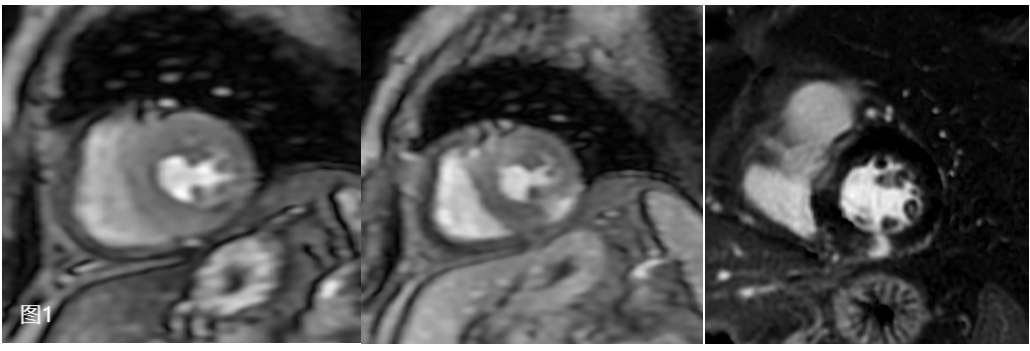

患者为一名60岁女性患者,因主诉“心前区疼痛5天”入院,患者为压榨性疼痛,伴胸闷、气短,休息后不能缓解。查心电图示窦性心律,ST-T段改变,肌钙蛋白超过2000pg/ml,临床考虑急性非ST段抬高型心肌梗死,入院冠状动脉DSA证实患者管腔前降支狭窄约50%,经心血管内科张岩副主任仔细分析患者病情,建议患者行药物负荷心肌磁共振灌注成像明确诊断。11月20日晚在大明宫院区,医学影像科丁墩副主任指导,徐增苗技师优化扫描序列,在患者有幽闭情绪的情况下,顺利使用瑞加诺生进行负荷MR心肌灌注成像,注射药物后1分钟后患者心率由70次/分上升至最高95次/分,扫描过程中严密监视患者心率及不良反应,随后顺利完成心脏电影、心肌延期增强扫描,患者自觉无任何其他不适,检查顺利完成。

经负荷心肌灌注显像提示患者左心室多节段可见心内膜下灌注缺损,延迟强化提示下壁透壁性心肌梗死,经磁共振心脏成像诊断为MINOCA,这也解释了患者心外膜冠状动脉主要分支未见明显狭窄,仍反复出现胸闷、胸痛等症状。目前患者经治疗,病情平稳顺利出院。